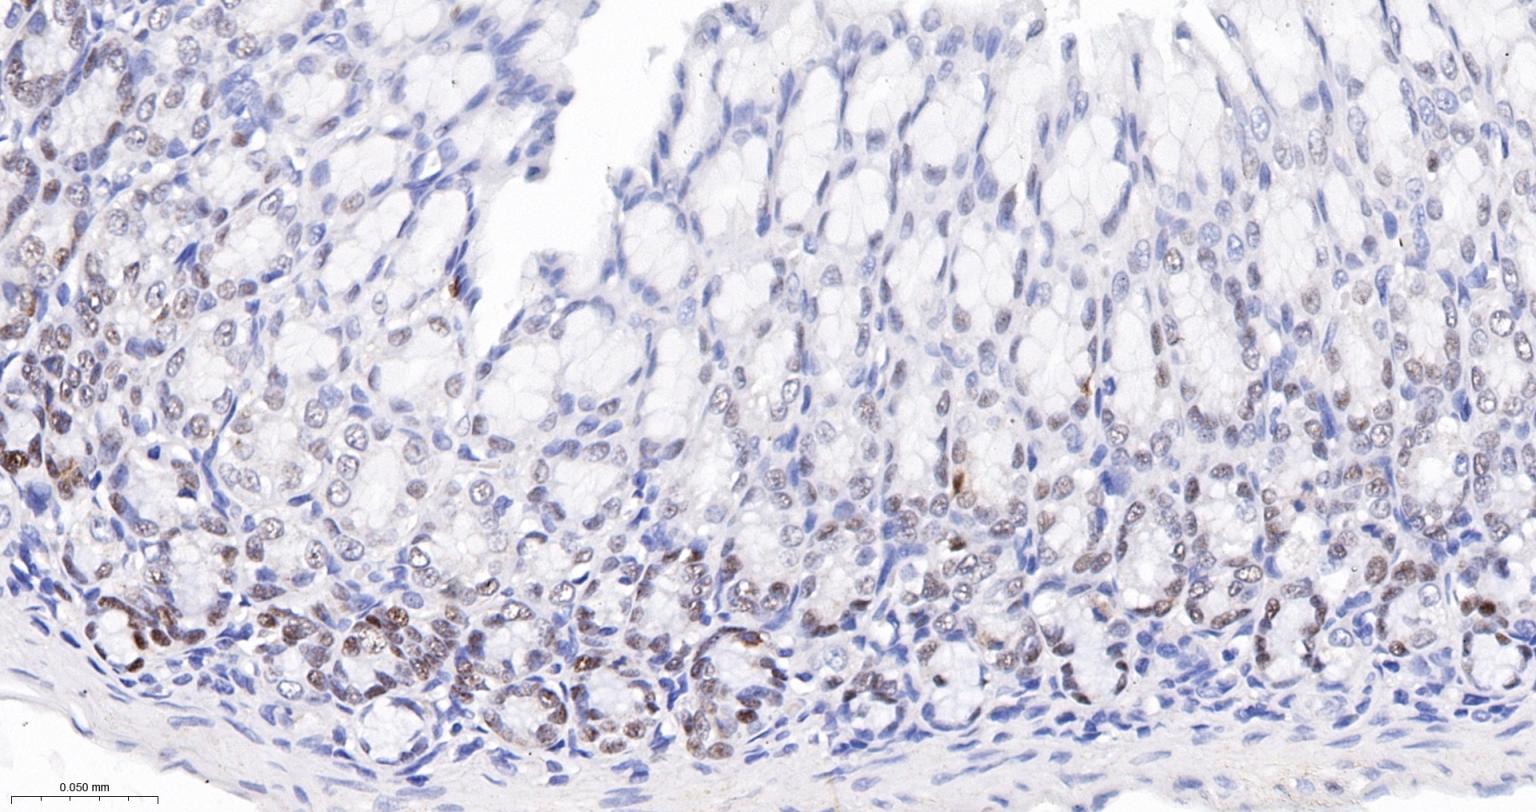

Paraformaldehyde-fixed, paraffin embedded Human Lung Cancer; Antigen retrieval by boiling in sodium citrate buffer (pH6.0) for 15 min; Antibody incubation with SOX2 Monoclonal Antibody, Unconjugated(bsm-60788R) at 1:300 overnight at 4°C, followed by conjugation to the SP Kit (Rabbit, SP-0023) and DAB (C-0010) staining.